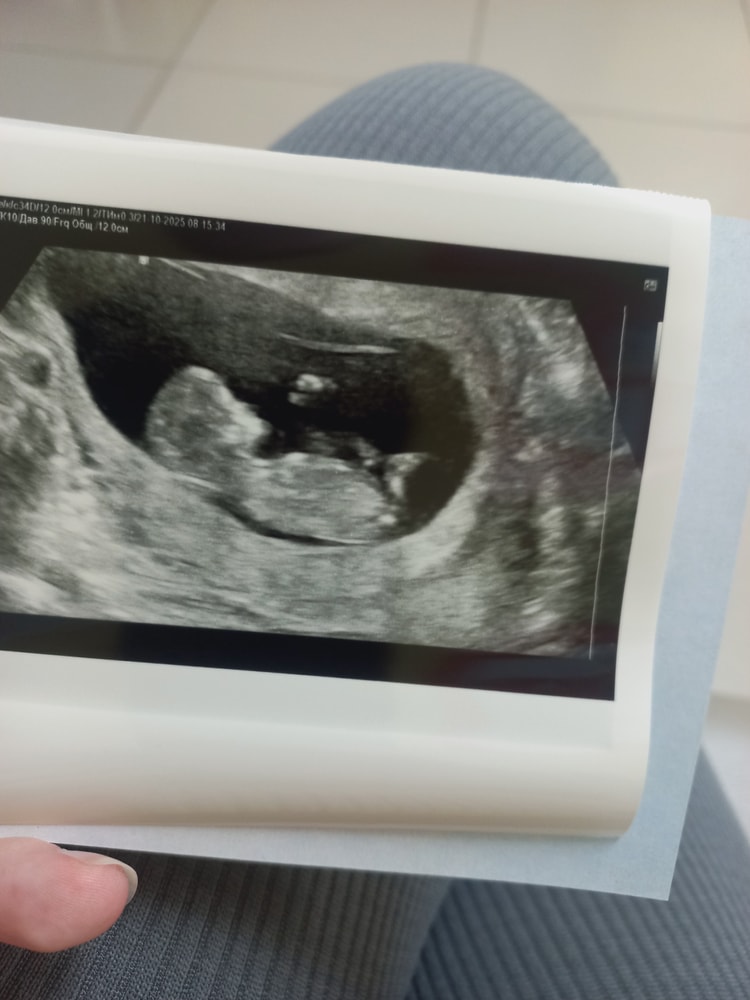

Узи скрининг 12 недель

Мой милипуська🥰опять еле поймали, всем там дрыгает, все оттеняется. За неделю вырос на 1.5 см😍

Ктр 5.4

Твп 1.2

Окружность головы 6.1

По узи здоров как бычок🤪